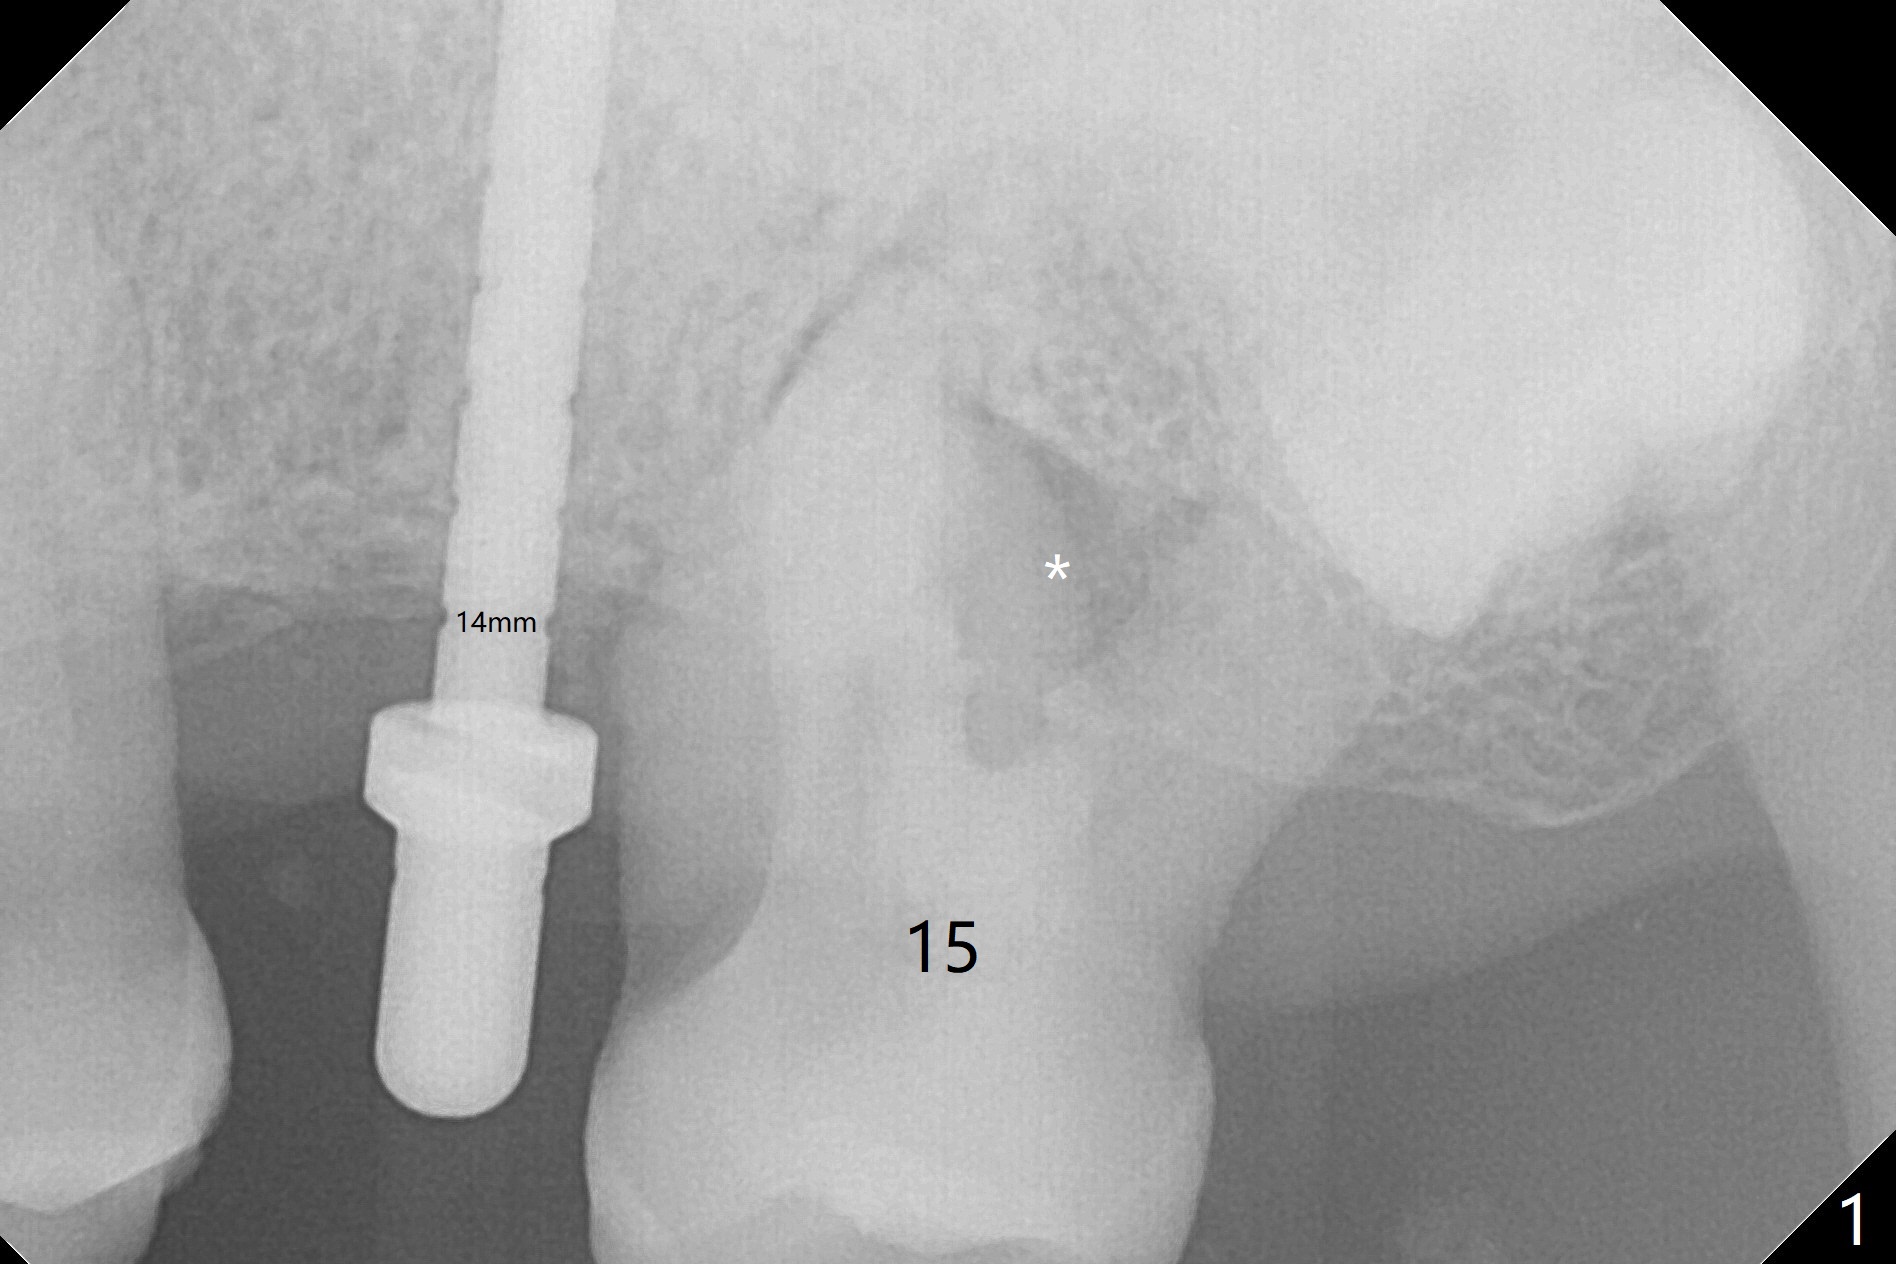

The patient is extremely nervous about implant placement at #14. Access is obtained with a 4 mm tissue punch, which appears to be the least traumatic. Since the gingiva is ~ 5 mm thick, vision is poor and it is difficult to change osteotomy buccally. It seems a 6 mm tissue punch is more appropriate for this case. The initial osteotomy depth is 14 mm (Fig.1). Since the tooth #15 is nonsalvageable because of furca caries and bone loss (Fig.1 *), the distal osteotomy at #14 is apparently acceptable. When a 5x13 mm implant is placed with >50 Ncm (Fig.2), the implant is subcrestal clinically except palatal (osteotomy not buccal enough), which is consistent with bitewing view (Fig.3). A 5.5x5 mm healing abutment is placed. Surprisingly the fearful patient does not experience any pain. Tissue punch is an atraumtic measure. A larger one (6 mm) allows more room to change osteotomy. The access can be closed with larger healing abutment. If this implant fails due to periimplantitis, it is due to palatal placement with too large the implant (5 mm vs. 4 mm at #3). Palpate the bone prior to changing next large drill when performing a flapless procedure. The implant seems to be osteointegrated 5 months postop; the furca caries (Fig.4 *) is taken care of before impression with a 4.5x5(4) mm abutment. Distal caries of the tooth #13 is found 10 months post cementation (Fig.5). Strict oral hygiene for prevention should have been given after composite for the furca of the tooth #15 (*).